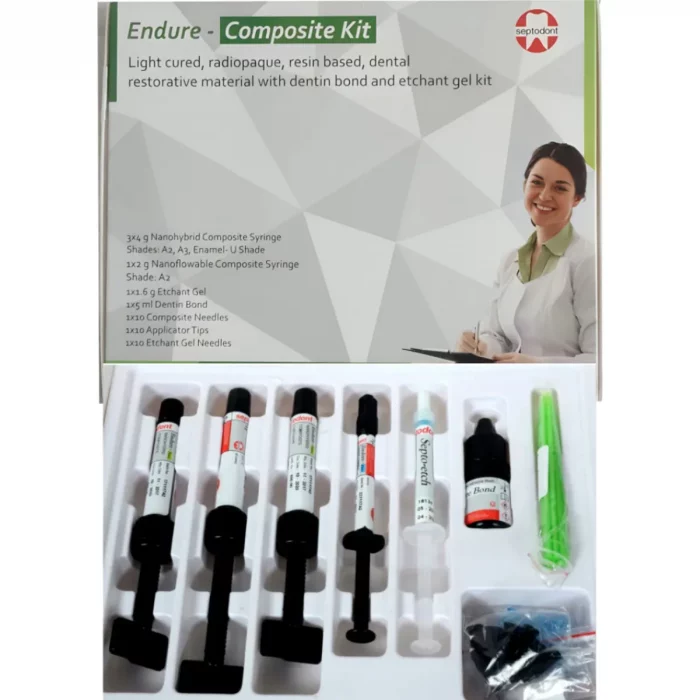

Packaging-

Septodont Endure Nano Hybrid Composite Kit

- 3X4 g Nanohybrid Composite Syringe Shades: A1, A2, B2

- 1×2 g Nanoflowable Composite Syringe Shade: A2

- 1×1.6 g Etchant Gel

- 1×5 ml Dentin Bond

- 1X5 Composite Needles

- 1X10 Applicator Tips

- 1×3 Etchant Gel Needles